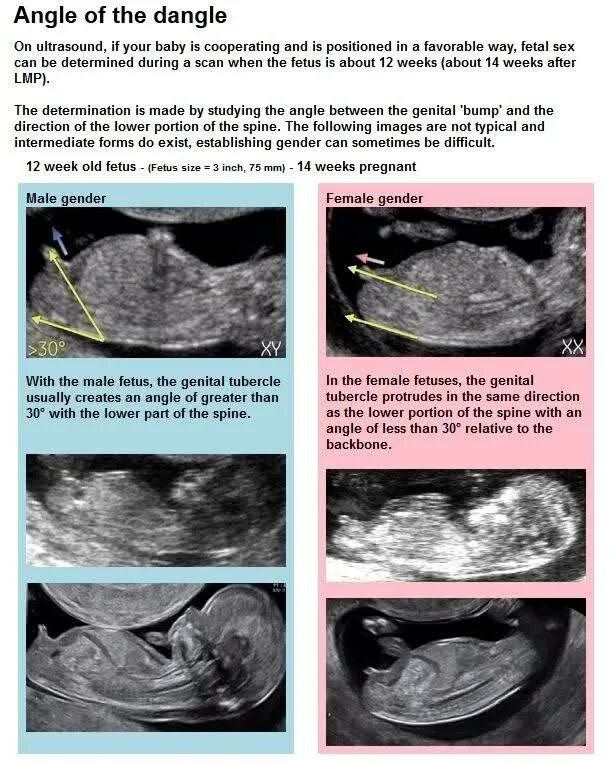

Как определить пол ребенка в 12 недель